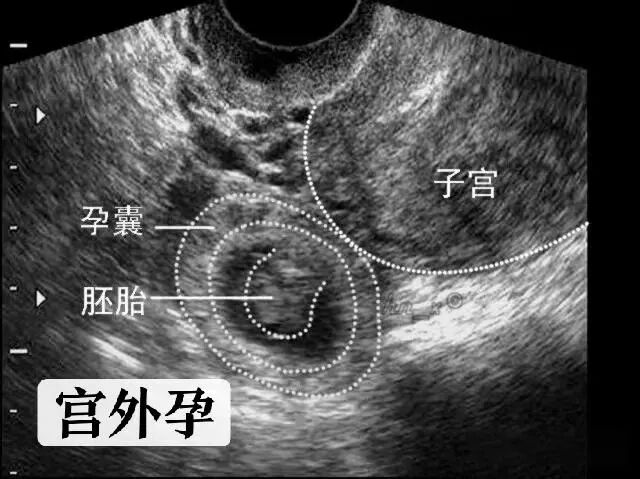

什么是异位妊娠?

异位妊娠的不同部位

95%为输卵管妊娠

迷路的宝宝

辅助检查:

HCG、孕酮检测、腹腔镜检查、经阴道后穹隆穿刺、诊断性刮宫。